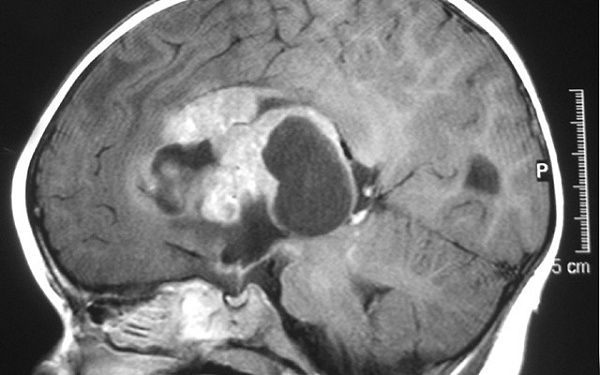

Атипичная тератоидно-рабдоидная опухоль (ATRT) – крайне редкая и быстро растущая форма рака головного мозга, которая обычно поражает детей в возрасте до 3 лет, хотя может встречаться и у детей старшего возраста и взрослых. Существует несколько видов лечения этой опухоли, однако нет оптимального стандарта оказания медицинской помощи, а прогноз выживаемости неутешительный. Возникновение ATRT в первую очередь связано с инактивацией гена SMARCB1, который участвует в регулировке экспрессии генов и различных процессов развития. В своей работе, опубликованной в журнале Genes and Development, исследователи из Калифорнийского университета в Сан-Диего и местного подразделения Института исследований раковых заболеваний им. Дэниэла Людвига, описали, как утрата функциональности этого гена сказывается на развитии нервной системы и росте опухоли.

Фото: Wikipedia